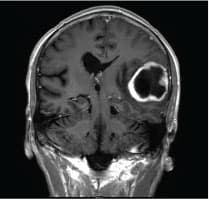

The pregnant woman was examined lying in a gynaecological position. The cervixes were examined in longitudinal planes using B-mode ultrasound to exclude any occult abnormality. Subsequently, RTE was performed using the same machine employing the extended, combined auto-correlation method (ECAM) [12]. RTE was performed by applying light repetitive compression with the hand-held vaginal transducer over the area of interest. During the compressions, the B-mode and the elastogramme were displayed side-by-side on the screen (Figure 1).

We divided the cervix into four parts: lower part P1, middle part P2, upper part P3 (about one third each) and the cervical channel (Figure 1). The cervical channel is visualized as integrated layers of green and red colours, which represent the cervical channel’s histological contents. Even the glandular ditches are visualized as red depressions.

The P1 area is dominated by green and to a lesser degree red. P2 contains a range of colours, primarily blue and green layers spread almost symmetrically around the cervical channel. In P3, the layered colour distribution continues with growing dominance of the blue color.

In consequence of the colour distribution and its relation to the tissue elasticity, we conclude that P1 is more elastic (mobile) than P3, and that the elasticity of P2 is a middle category between the two others. Consequently, the elasticity of the cervix increases towards the portio.

The strain rate (A) in P1 is higher than the strain rate (B) in P3, which fits with the colour distribution (Figure 1). The strain rate could be used as a comparative index among different areas rather than as an absolute strain measurement. These results can also be demonstrated using the strain levels displayed as box plots (median, interquartile range and minimum-maximum) shown in Figure 2, which demonstrates the above-mentioned association with the highest strains being the softest (more elastic). The median/mean strain rates (interquartile range/standard deviation) corresponding to Figure 2 are: P1A 0.49/0.61 (0.31-0.90/0.41), P2A 0.56/ 0.62 (0.32-0.73/0.46), P2B 0.27/0.33 (0.13-0.54/0.24) and P3B 0.14/0.21 (0.06-0.39/0.19). Stratification on previous preterm birth, deliveries, or gestational age at assessment did not change the pattern shown in Figure 2. Due to too few cases, statistical analyses are not meaningful. It is therefore not possible to draw conclusions regarding any elastographic changes in the cervix at different ages of gestation or any correlations with the length of the cervix.